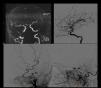

Se presenta un caso de aneurisma gigante no traumático de la arteria meníngea media en un paciente de 59años con antecedentes de trasplante hepático, cirrosis hepática y hepatocarcinoma, enfermedad renal crónica, HTA y bronquitis crónica que ingresó por presentar crisis tónico-clónica. La TC y la RM mostraron una lesión sugestiva de metástasis sin descartar un tumor de tipo glial. Fue intervenido mediante una craneotomía FT izquierda. Durante la cirugía se produjo una hemorragia arterial. La muestra histológica orientó hacia un origen aneurismático que se confirmó con ARM y angiografía. Una segunda intervención permitió la extirpación de un aneurisma gigante de la arteria meníngea media parcialmente trombosado. Los aneurismas de la arteria meníngea media son raros y en general presentan un antecedente traumático. No se ha encontrado en la literatura médica ningún caso de aneurisma gigante.

A case of a non-traumatic giant aneurysm of the middle meningeal artery is presented in a 59-year-old patient with a history of liver transplantation, liver cirrhosis and hepatocarcinoma, chronic renal disease, hypertension and chronic bronchitis who presented with tonic-clonic seizures. CT and MRI showed a lesion suggestive of metastasis without ruling out a glial type tumor. He was operated through a left FT craniotomy. During the surgery there was an arterial hemorrhage. The histological sample oriented toward an aneurysmal origin that was confirmed with ARM and angiography. A second intervention allowed the removal of a giant middle meningeal aneurysm partially thrombosed. Aneurysms of the middle meningeal artery are rare and generally present a traumatic history. No case of giant aneurysm has been found in the medical literature.